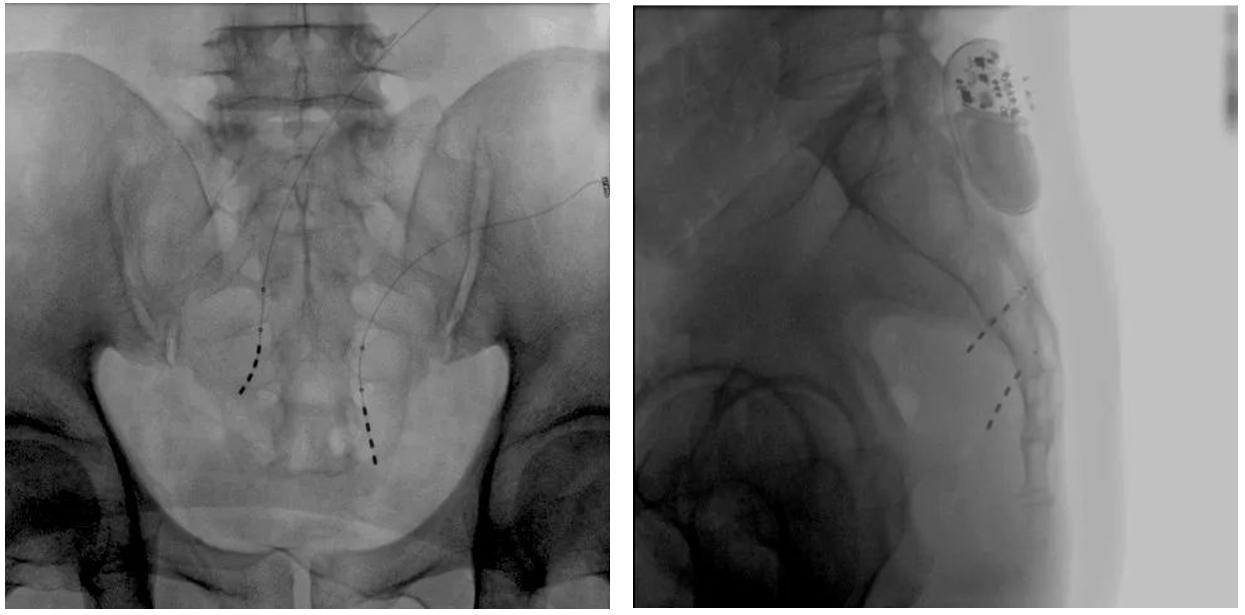

该患者两年前被诊断患有膀胱过度活动症(OAB),出现严重尿频、尿急、尿细线等症状,医生为其做了骶神经调控手术。近期,患者症状又开始加重,生活质量受到影响,为减轻症状,改善生活,患者前往南医大二附院就诊。卫中庆主任及其团队在查看患者病情后,决定重新调整电极刺激位置,将刺激点由原左侧骶4神经孔改为骶3神经孔,通过新的神经调节顺利地改善了症状。

患者术前影像

大平板一体式移动C形臂术中影像

在骶神经调控术或者骶神经刺激术(SNS)中,医师首先会在透视引导下把电极通过导针插入到骶3神经孔位置,通过脉冲电流的刺激,达到兴奋神经纤维并抑制逼尿肌收缩。在这一步,医师会先对患者的神经刺激反应做测试评估,如果刺激效果明显,说明该方案能够达到手术预期。接下来医师会在附近皮下脂肪处植入一块脉冲电流发生器并与电极相连,使该部位今后能得到长期的电刺激,改善OAB症状。